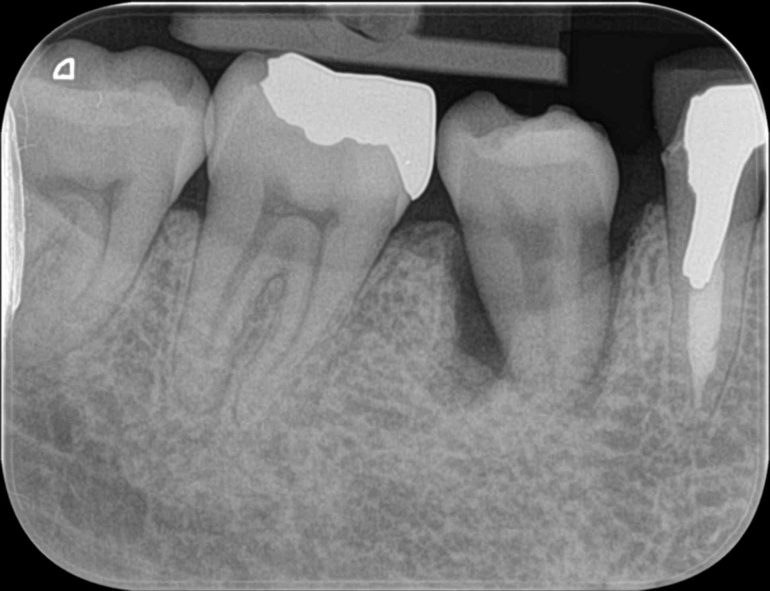

ここからはレントゲンでの変化を追っていきます。

ますは抜歯前。歯の根が折れてしまっていました。

移植後すぐのレントゲンです。3Dプリンターでのレプリカを使って、移植する歯が一番安定し、かつ前後の歯と調和が取れる場所を探しています。

移植後2週間で根管治療後のレントゲンです。まだまだ移植している歯の周辺には骨はできておりませんが、歯の動揺(動き)は少なくなってきています。